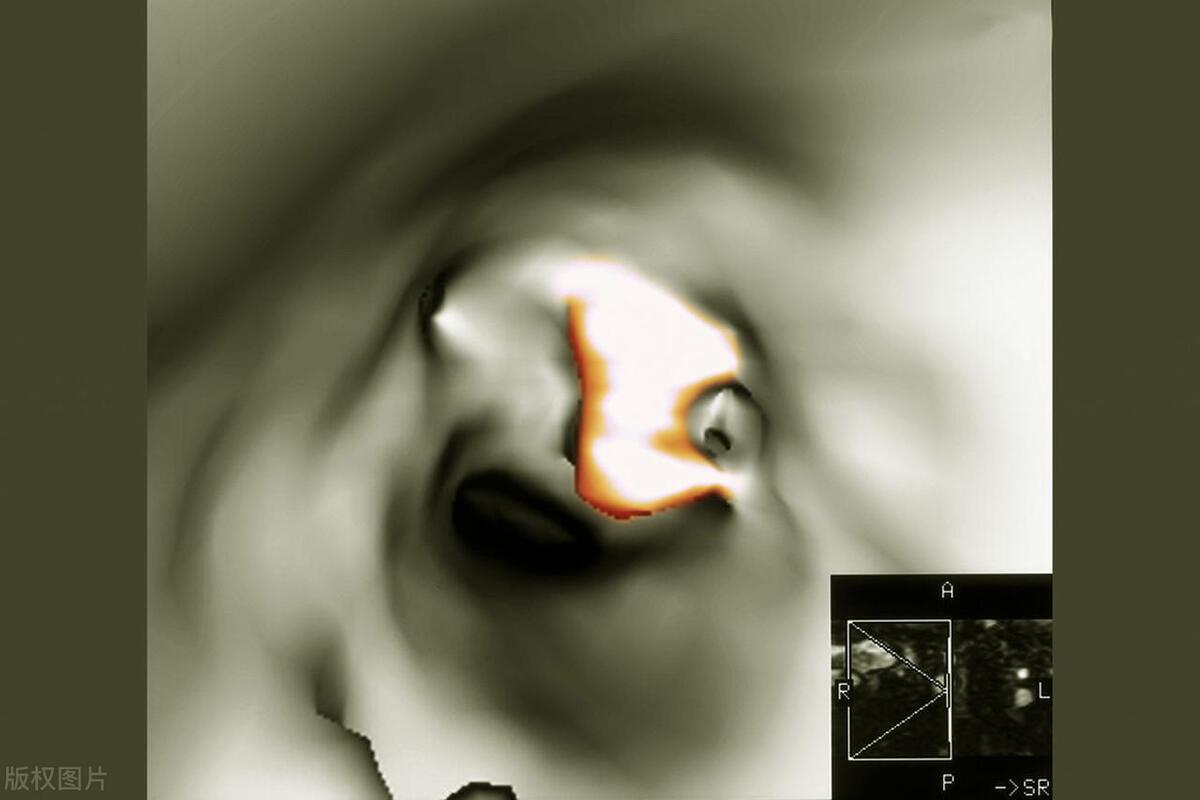

目前最常用的是颈动脉超声检查 ,这种检查不需手术,非常 快速而且方便还比较经济 的。

可以 初步筛选颈动脉斑块易患的高风险人群 ,对血管的狭窄程度进行评估,判断斑块的性质。

血管造影虽然费用较高,有一定风险,但的优点是 可以直接地看到血管的形状和变窄的程度。